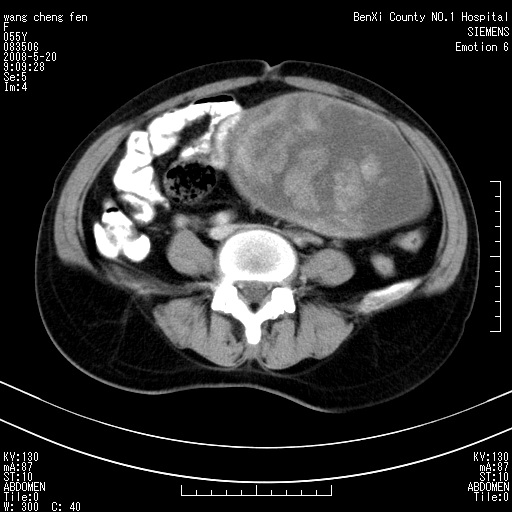

女、绝经后阴道流血3个月

左侧附件区可见一囊性占位,边缘清楚,内可见不规则形软组织影 ce:囊壁及内部可见强化 考虑 卵巢囊腺瘤

左侧附件区巨大囊实性病灶,边缘光整,病灶囊壁较厚,增强示囊壁及实性部分明显强化,强化呈度与宫体实质大致相同,宫腔积液征像,未见盆腔积液等其他异常,考虑左侧卵巢囊腺癌,不除外囊腺瘤及浆膜下肌瘤坏死

左侧附件区巨大囊实性病灶,边缘光整,病灶囊壁较厚,增强示囊壁及实性部分明显强化,强化呈度与宫体实质大致相同,宫腔积液征像,未见盆腔积液等其他异常。绝经后阴道流血3个月,结合病史左侧卵巢囊腺癌首先考虑,宫腔扩大不除外累及。期待结果。

囊实性肿块分隔厚度较大,厚薄不均,增强实性成分明显强化,有不规则阴道流血,卵巢囊腺癌可能性大。